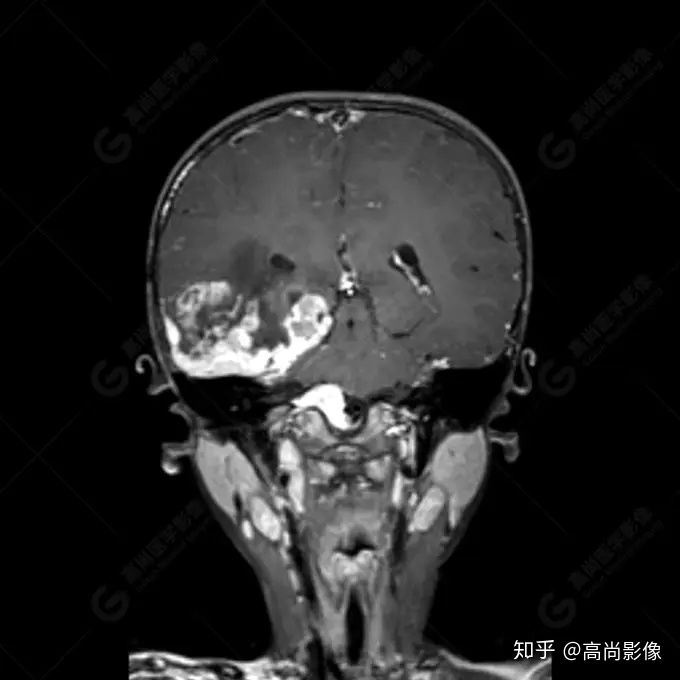

右側(cè)顳葉腫瘤切除術(shù)后(具體不詳):右側(cè)顳部骨質(zhì)不連續(xù)呈術(shù)后改變,右側(cè)顳葉術(shù)區(qū)見片狀長(zhǎng)T1長(zhǎng)T2信號(hào)影,F(xiàn)LAIR呈低信號(hào);術(shù)區(qū)后方右側(cè)顳枕葉見一巨大占位性病變影,邊界欠清,大小約6.2×5.8×4.3cm(前后×左右×上下),信號(hào)不均勻,T1WI呈等稍低信號(hào)間雜少許高信號(hào),T2WI呈高稍低混雜信號(hào),DWI示部分病灶彌散受限,相應(yīng)ADC圖減低,磁敏感序列見部分呈極低信號(hào),增強(qiáng)掃描可見明顯不均勻強(qiáng)化,鄰近硬腦膜及小腦幕增厚并明顯強(qiáng)化;另延髓右前方及右側(cè)橋小腦角區(qū)見一不規(guī)則形異常信號(hào)影,大小約3.2×1.3×3.7cm(左右×前后×上下),呈長(zhǎng)T1稍長(zhǎng)T2信號(hào),F(xiàn)LAIR呈等信號(hào),DWI未見受限,增強(qiáng)后明顯均勻強(qiáng)化,鄰近腦膜明顯強(qiáng)化。鄰近腦實(shí)質(zhì)及右側(cè)顳角明顯受壓;左側(cè)大腦半球未見局灶性信號(hào)異常,中線結(jié)構(gòu)稍左移。

右側(cè)顳葉腫瘤切除術(shù)后:現(xiàn)術(shù)區(qū)后方右側(cè)顳枕葉及延髓右前方占位,右側(cè)顳枕部硬腦膜及小腦幕明顯強(qiáng)化,結(jié)合既往影像資料,考慮為胚胎源性惡性腫瘤,如非典型畸胎樣/橫紋肌樣瘤(AT/RT)或原始神經(jīng)外胚層腫瘤(PNET)。